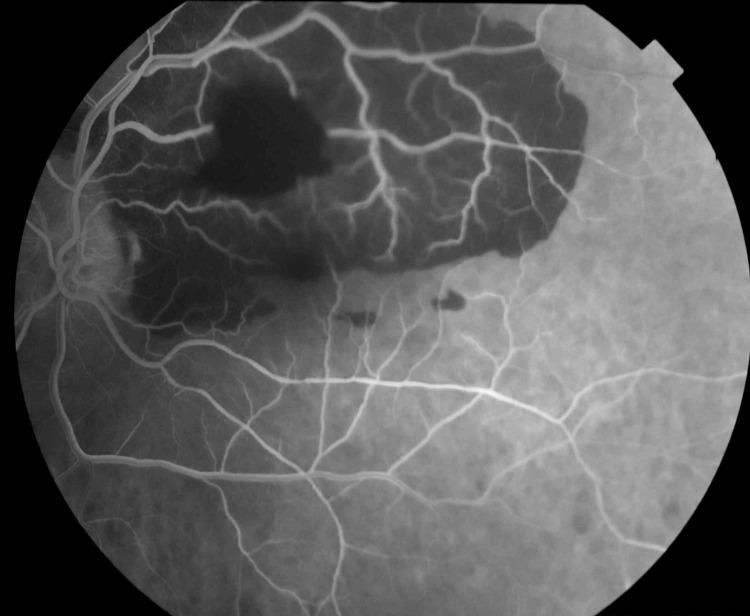

视网膜动脉大动脉瘤破裂继发多层出血:一例报告并文献复习

Multilayered Hemorrhage Secondary to Retinal Arterial Macroaneurysm Rupture: A Case Report and Review of Literature.

Retinal arterial macroaneurysms represent an acquired vascular irregularity that is primarily observed in the elderly population. The high variability surrounding the clinical presentation of this condition makes the initial diagnosis challenging. Employing several diagnostic techniques including fundus fluorescence angiography, optical coherence tomography, and optical coherence tomography angiography ensures that any hemorrhages secondary to macroaneurysms rupture are identified promptly. This is crucial for appropriately managing the case and ensuring a good prognosis. Here, we present a case of a multilayered hemorrhage secondary to a ruptured retinal arterial macroaneurysm managed with a pars plana vitrectomy with gas tamponade and we aim to highlight the recent advancements in diagnosis and management of this condition.

摘要